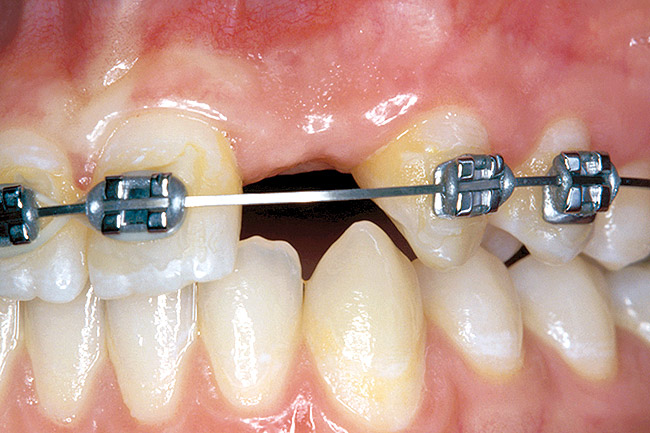

Before the day of surgery, the patient was seen by the orthodontist for the removal of the orthodontic brackets. The patient still was not pleased with the position of the two centrals, and it was determined that this would be addressed after implant placement (Figure 26). The anatomical variations of the crestal tissue and lack of interdental papilla can be appreciated in the close-up views of the right and left sites (Figure 27 and Figure 28). There were no surprises on the day of surgery as all of the decisions were made during the planning phase, before the scalpel ever touched the patient. The occlusal view of the CT 3D model revealed the wider alveolar ridge on the right side and thinner crest on the left side (Figure 29). This was confirmed when the full-thickness mucoperiosteal flaps were elevated, and the underlying bone revealed (Figure 30). The tooth-borne templates were designed to facilitate the drills and drilling sequence specific to the diameters of the predetermined implants (Figure 31). Each template contained an embedded 5-mm long stainless steel tube, which was approximately 0.2-mm wider than each drill (just wide enough to allow for the drills to rotate freely). Once positioned over the natural teeth, the template was secure and offered precision accuracy in transferring the implant locations from the original software-designed plan, allowing the potential for internal and external irrigation (Figure 32).

Figure 26  VIRTUAL PLANNING AND SURGERY Before implant surgery, the orthodontic brackets were removed, revealing the position of the centrals, and the anatomical variations of the crestal tissue and lack of interdental papilla.

Figure 26

Figure 27   VIRTUAL PLANNING AND SURGERY Before implant surgery, the orthodontic brackets were removed, revealing the position of the centrals, and the anatomical variations of the crestal tissue and lack of interdental papilla.

Figure 27

Figure 28   VIRTUAL PLANNING AND SURGERY Before implant surgery, the orthodontic brackets were removed, revealing the position of the centrals, and the anatomical variations of the crestal tissue and lack of interdental papilla.

Figure 28